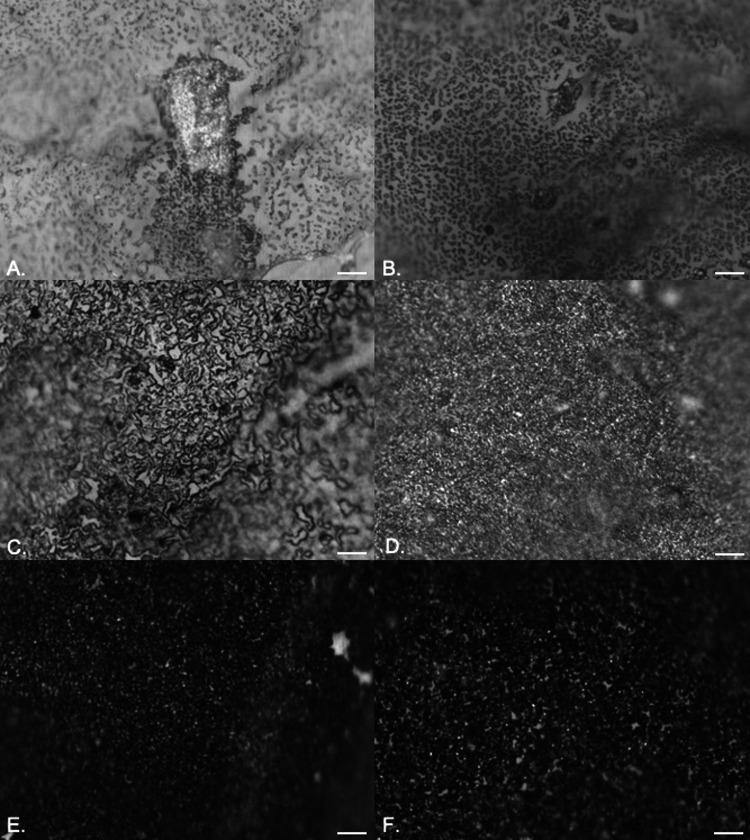

Catheter-associated urinary tract infections have serious consequences, for both patients and health care resources. Much work has been carried out to develop an antimicrobial catheter. Although such developments have shown promise under laboratory conditions, none have demonstrated a clear advantage in clinical trials. Using a range of microbiological and advanced microscopy techniques, a detailed laboratory study comparing biofilm development on silicone, hydrogel latex, and silver alloy-coated hydrogel latex catheters was carried out. Biofilm development by , , and on three commercially available catheters was tracked over time. Samples were examined with episcopic differential interference contrast (EDIC) microscopy, culture analysis, and staining techniques to quantify viable but nonculturable (VBNC) bacteria. Both qualitative and quantitative assessments found biofilms to develop rapidly on all three materials. EDIC microscopy revealed the rough surface topography of the materials. Differences between culture counts and quantification of total and dead cells demonstrated the presence of VBNC populations, where bacteria retain viability but are not metabolically active. The use of nonculture-based techniques showed the development of widespread VBNC populations. These VBNC populations were more evident on silver alloy-coated hydrogel latex catheters, indicating a bacteriostatic effect at best. The laboratory tests reported here, which detect VBNC bacteria, allow more rigorous assessment of antimicrobial catheters, explaining why there is often minimal benefit to patients. Several antimicrobial urinary catheter materials have been developed, but, although laboratory studies may show a benefit, none have significantly improved clinical outcomes. The use of poorly designed laboratory testing and lack of consideration of the impact of VBNC populations may be responsible. While the presence of VBNC populations is becoming more widely reported, there remains a lack of understanding of the clinical impact or influence of exposure to antimicrobial products. This is the first study to investigate the impact of antimicrobial surface materials and the appearance of VBNC populations. This demonstrates how improved testing is needed before clinical trials are initiated.